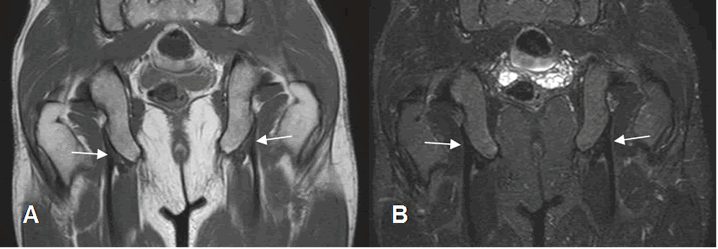

Los tendones de todos los grupos musculares, se aprecian como estructuras hipointensas en todas las secuencias, en relación con los sitios de origen e inserción. (Fig 21, 22 y 23).

Fig 21. Músculos normales.

A: RM coronal en T1 y B: RM coronal en STIR. Origen de músculos isquiotibiales, hipointensos en todas las secuencias.